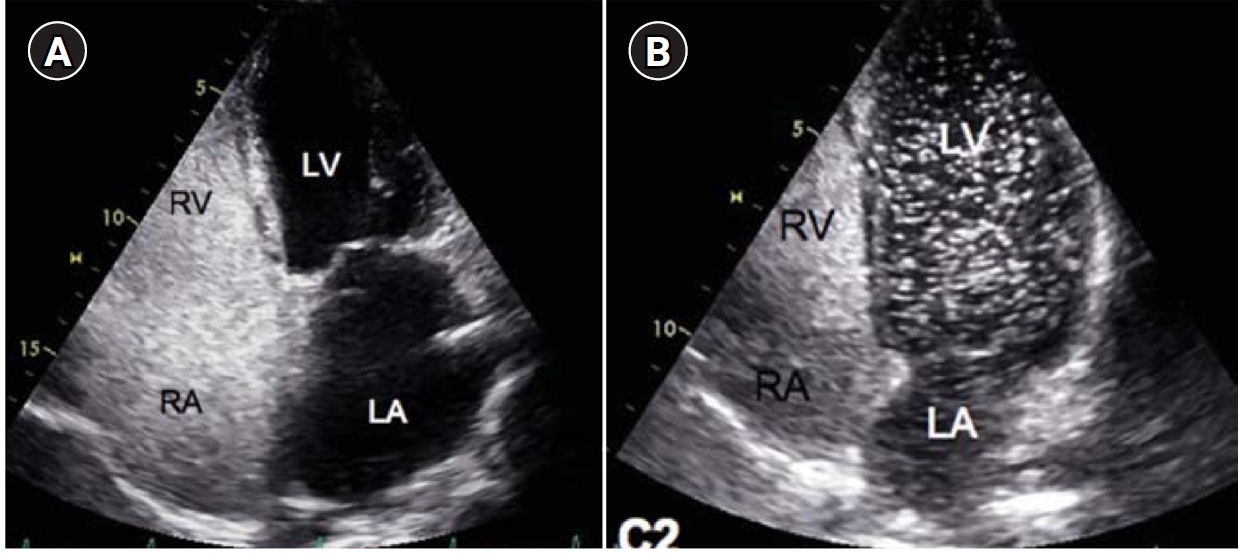

Fig. 2.

Embolization of a 1.5-mm feeding artery associated with an arteriovenous malformation in the left upper lobe of a 36-year-old female patient. (A) On the computed tomography (CT), a slender 1.5 mm feeding artery to the left upper lobe (black arrows) and a dilated venous sac (white arrow) are visible. (B) On angiography, the same finding as on the CT is observed (black arrows and white arrow), (C, D) A scene of coil embolization (C) and a post-embolization angiography image (D). In panel (D), the tri-axial system was utilized, including a 6-Fr Shuttle guiding catheter, a 5-Fr angled catheter, and a 1.9-Fr microcatheter, to access the feeding artery. Coil embolization was performed using Concerto 3D and Helix coils.

To prevent paradoxical embolism or life-threatening bleeding, all detected PAVMs should be treated in adult patients. Historically, a feeding artery diameter of ‘3 mm’ was considered the minimal diameter criterion for treatment of PAVMs [2]. However, with advances in embolic devices and catheter systems, less than 3 mm feeding arteries ≥2 mm can now be embolized (Fig. 2) [11]. Pregnancy is a special risk factor in patients with PAVM, especially in the second and third trimesters due to a decrease in peripheral vascular resistance and an increase in cardiac output by nearly 50% [12]. A recent study in 244 pregnant women with HHT showed major complications in 13%, all in patients who had not been screened or treated for PAVMs prior to pregnancy [13]. Thus, all women with HHT considering pregnancy should be screened for PAVM with computed tomography (CT) and eventually treated prior to conception.

Historically, detachable balloons were used as an embolization material; however, they are no longer utilized in current practice [18]. In the context of PAVM embolization, the use of coils, vascular plugs, or a combination of both is now standard practice [19-21]. Since the development of detachable coils, they have offered advantages over pushable coils, particularly in terms of repositioning during the procedure. They can even be fully retrieved and redeployed if necessary, enhancing procedural safety and control. It is crucial to prioritize minimizing the recanalization rate while ensuring the overall safety of the procedure when selecting the appropriate embolic materials and techniques. Feeding artery coil embolization was historically regarded as the standard approach, whereas venous sac embolization was discouraged because of the perceived risk of rupture [22]. However, with the introduction of newer venous sac embolization techniques, recent findings now indicate that tightly packing the venous sac with coils can achieve a higher success rate than the traditional feeding artery approach (Fig. 2) [22-25]. Additionally, vascular plugs, including micro-vascular plugs (Medtronic, Minneapolis, MN, USA) and Amplatzer vascular plugs (Abbott Vascular, Saint Paul, MN, USA) have also demonstrated a higher success rate compared to feeding artery coil embolization (Fig. 4) [26-28]. In the case of vascular plugs, the risk of device migration is relatively low. Moreover, an additional advantage is that the device can be repositioned if the sizing is not ideal or if it is not deployed in the exact desired location. This flexibility enhances the precision of the procedure (Fig. 5). In a recent European guideline, there is also a recommendation to consider vascular plug embolization as a first-line option whenever possible, rather than coil embolization [11]. Additionally, a recent meta-analysis recommended vascular plugs or venous sac coil embolization, noting that vascular plugs had a recanalization rate of 13.6% compared to 32.7% for coil-only embolization. Similarly, venous sac embolization showed a 3.8% recanalization rate, while feeding artery embolization had a rate of 24.3%. Additionally, a recent meta-analysis has recommended the use of vascular plug or venous sac coil embolization, as these techniques have demonstrated a lower persistence rate compared to other methods [21]. This shift is largely in response to the relatively high recanalization rate associated with feeding coil embolization. In the case of embolization using vascular plugs, the plug should be deployed at the most distal segment of the feeding artery just before the venous sac in order to preserve the normal pulmonary artery. Since the pulmonary artery contains less elastin and has a thinner wall compared to systemic arteries, it is more distensible [29]. Therefore, in the author's experience, oversizing by about 50% to 100% has been effective in reducing the recanalization rate. When performing venous sac coil embolization, it is important to use coils large enough to create a stable framing coil larger than the draining vein diameter, thereby preventing coil migration. After establishing this frame, the venous sac and the proximal feeding artery should be carefully packed to achieve complete occlusion.

Fig. 2. Embolization of a 1.5-mm feeding artery associated with an arteriovenous malformation in the left upper lobe of a 36-year-old female patient. (A) On the computed tomography (CT), a slender 1.5 mm feeding artery to the left upper lobe (black arrows) and a dilated venous sac (white arrow) are visible. (B) On angiography, the same finding as on the CT is observed (black arrows and white arrow), (C, D) A scene of coil embolization (C) and a post-embolization angiography image (D). In panel (D), the tri-axial system was utilized, including a 6-Fr Shuttle guiding catheter, a 5-Fr angled catheter, and a 1.9-Fr microcatheter, to access the feeding artery. Coil embolization was performed using Concerto 3D and Helix coils.